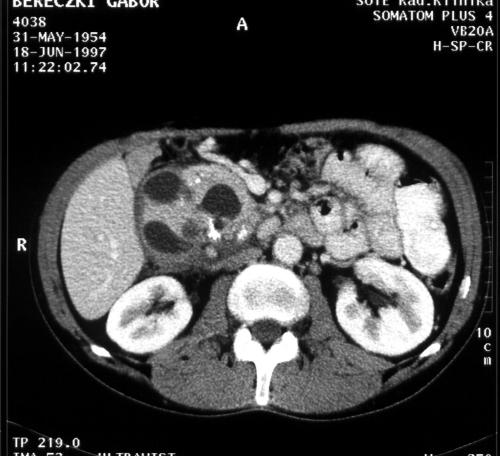

Figure 4. A 45 year old male alcoholic with epigastric pain. CT of the pancreas shows an enlarged pancreatic head, with multiple cystic degeneration and calcification. Chronic pancreatitis

Pancreatic swelling of the entire gland with calcification is the typical picture of chronic pancreatitis. Occasionally, an isolated mass of the pancreatic head can be found. The dilatation of the pancreatic duct is a typical finding and can be better demonstrated after administration of contrast material. The contours of the pancreatic duct are more irregular than in tumor related obstructions. Contrast enhancement of the parenchyma is non-homogeneous due to fibrosis.

The typical CT appearance of pancreatic pseudocysts are a hypodense lesion with a well demarcated, sometimes thick, wall [17].